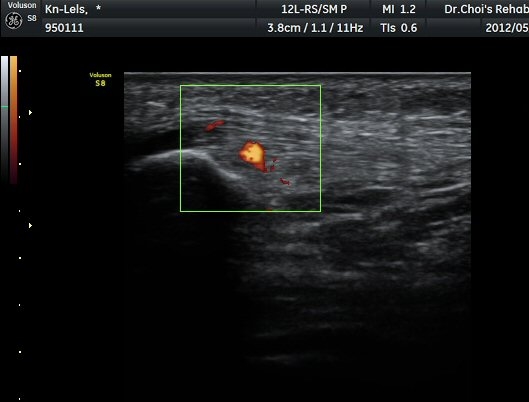

ÈûÁÙÀÇ ºñÈÄ´Â °ÇÃø(±×¸² 5)°ú ºñ±³ÇÏ¸é ¶Ñ·ÈÇϰí, ÆÄ¿öµµÇ÷¯°Ë»ç¿¡¼­ ÈûÁÙ³»¿¡

Ç÷·ùÁõ°¡µµ È®ÀδϵȴÙ(±×¸² 6, 7).